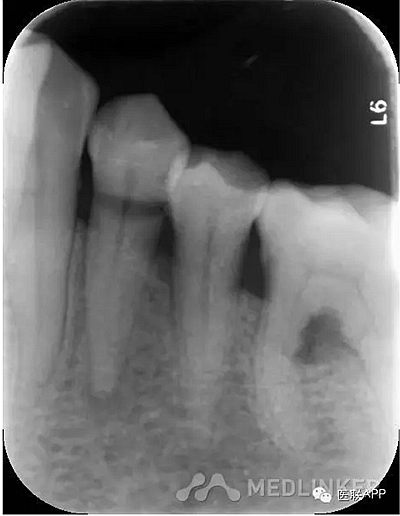

34頰側楔狀缺損達髓腔,可探及穿髓孔,探痛(-),叩痛(+),松動I度。

X線示:34根尖周小面積低密度影。

診斷:34慢性根尖周炎